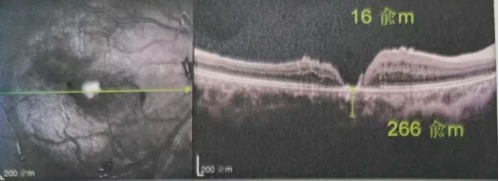

由于自身患有頸椎病,每次術(shù)后長(zhǎng)期的趴睡都讓他痛苦不堪。為了尋求更好的治療,吳爺爺來到廈門大學(xué)附屬?gòu)B門眼科中心,找到了眼外傷及眼底病2科的李海波博士后。此時(shí),吳爺爺右眼的黃斑裂孔已經(jīng)持續(xù)擴(kuò)大到780μm,演變?yōu)殡y治性的大裂孔。

最讓吳爺爺難以置信的是:術(shù)后只需保持平躺24小時(shí)!第二天復(fù)查時(shí),眼底鏡及OCT檢查清晰顯示——那個(gè)折磨了他大半年的大裂孔,竟然閉合了!且吳爺爺?shù)挠已垡暳τ辛嗣黠@的改善,術(shù)后3天已經(jīng)可以看到 0.15。